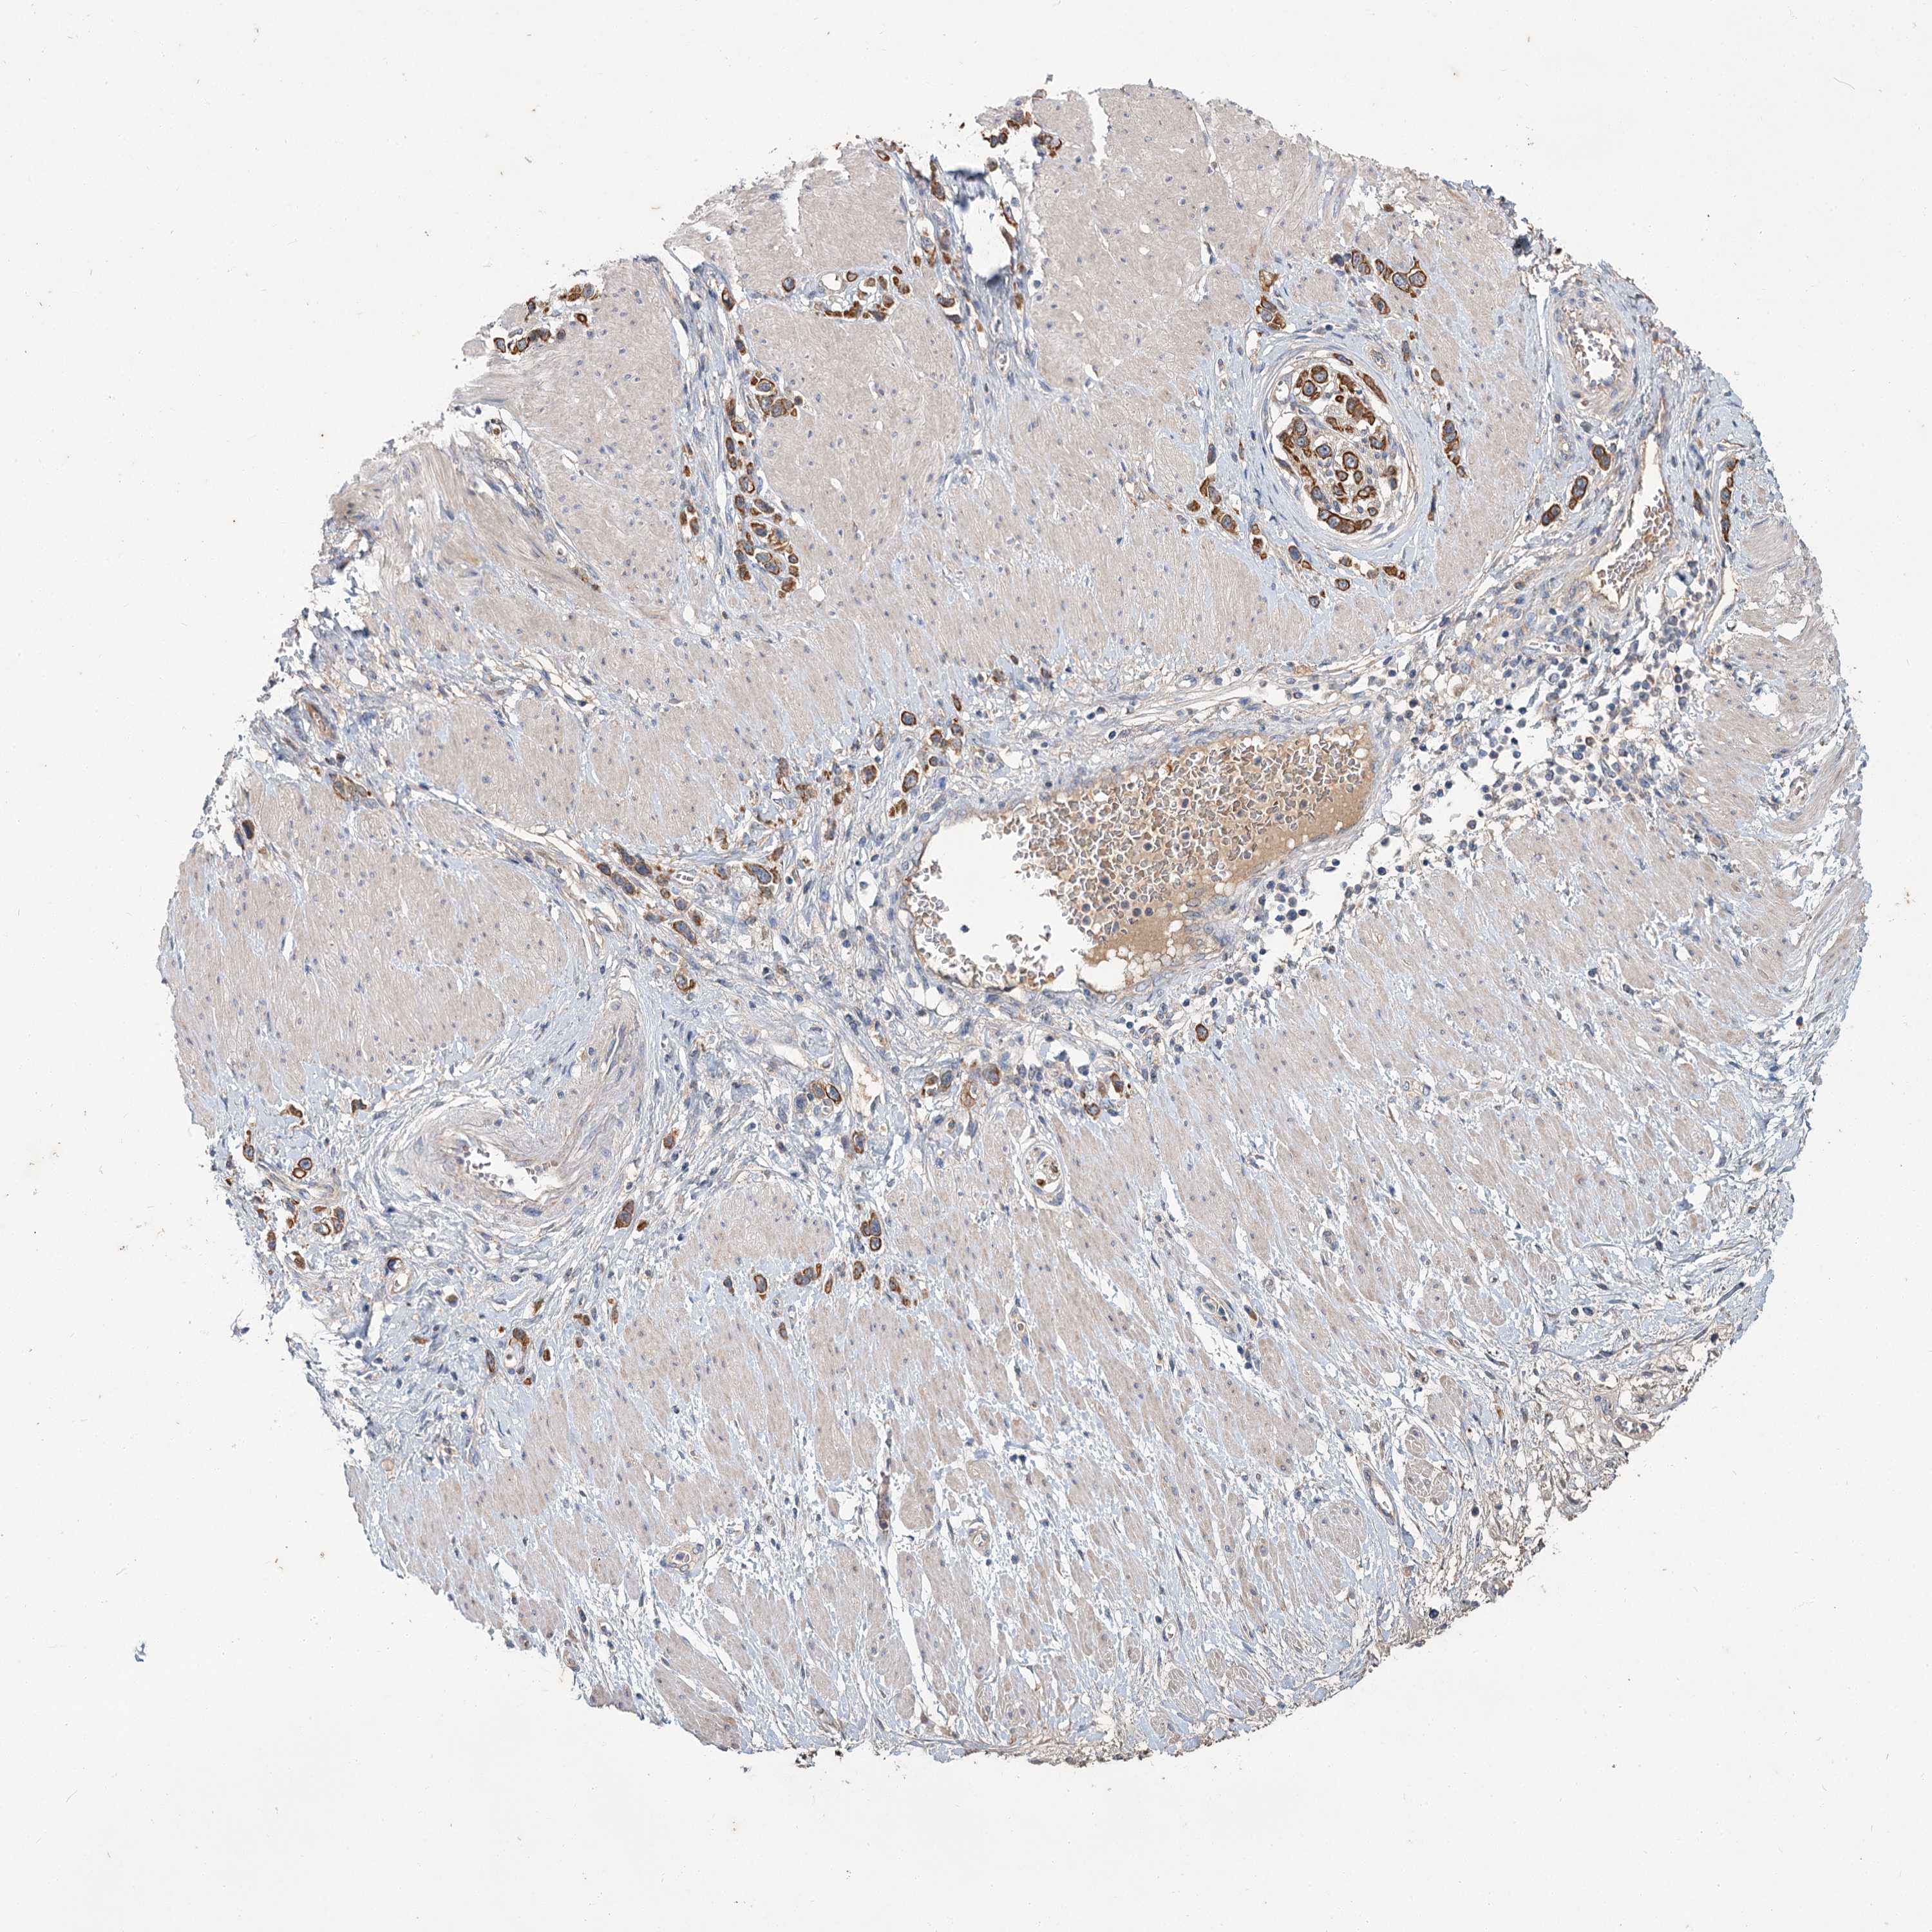

STOMACH CANCER - Protein expressioni

A mouse-over function shows sample information and annotation data. Click on an image to view it in a full screen mode. Samples can be filtered based on level of antibody staining by selecting one or several of the following categories: high, medium, low and not detected. The assay and annotation is described here.

Note that samples used for immunohistochemistry by the Human Protein Atlas do not correspond to samples in the TCGA dataset.

Antibody stainingi

Antibody staining in the annotated cell types in the current human tissue is reported as not detected, low, medium, or high, based on conventional immunohistochemistry profiling in selected tissues. This score is based on the combination of the staining intensity and fraction of stained cells.

Each image is clickable and will lead to virtual microscopy that enables deeper exploration of all samples and also displays staining intensity scores, fraction scores and subcellular localization as well as patient and tissue information for each sample.

Antibody CAB033437

Staining

High

Medium

Low

Not detected

Intensity

Strong

Moderate

Weak

Negative

Quantity

>75%

75%-25%

<25%

None

Location

Nuclear

Cytoplasmic/membranous

Cytoplasmic/membranous,nuclear

Adenocarcinoma, NOS